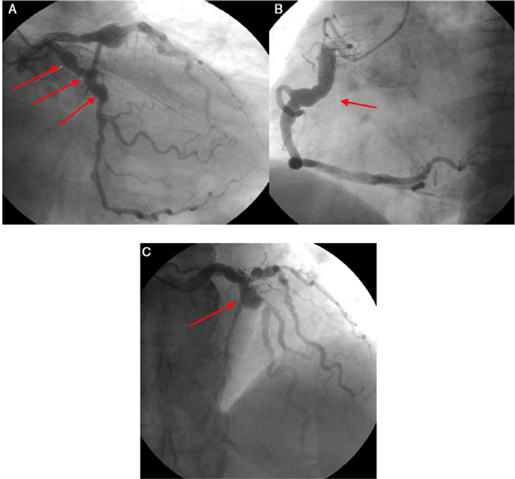

Se realizó angiografía coronaria en la que se hicieron los siguientes hallazgos: Tronco: angiográficamente normal; arteria descendente anterior: tipo III, aneurisma en su tercio proximal, buen vaso distal. Presencia de flujo lento TIMI conteo TFC de 43; arteria circunfleja: dilataciones aneurismáticas en todo su trayecto, con placas distales no significativas y presencia de flujo lento TIMI conteo TFC de 50; arteria coronaria derecha: vaso dominante, con gran aneurisma en tercio proximal y medio. Ectasia distal sin lesiones obstructivas y presencia de flujo lento TIMI conteo TFC de 47 (fig. 2).

Figura 2 A. Múltiples dilataciones aneurismáticas en la arteria circunfleja. (flechas). B. Arteria coronaria derecha con ectasia en su tercio proximal y medio (flecha). C. Aneurisma en la arteria descendente anterior en su tercio proximal (flecha).